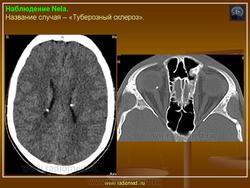

Туберозный склероз

Туберозный склероз (болезнь Бурневилля-Прингла, синдром Бурневилля - Брессау) - глиоз белого вещества мозга, проявляющийся в раннем детстве эпилептическими припадками (в 85%), олигофренией в сочетании с нараста­ющей пирамидной и экстрапирамидной симптоматикой, кожной патологией. В возрасте 4-6 лет на лице в форме бабочки в области носа обычно появляют­ся множественные желто-розовые или коричнево-красные узелки диаметром чуть больше 1 мм - аденомы Прингла, которые обычно признаются аденомами сальных желез, однако есть мнение и о том, что они представляют собой про­исходящую из нервных элементов кожи гамартрому.

Встречаются и аномалии развития извилин мозга в виде микро- и пахигирии. Заболевание чаще носит спорадический характер. Бляшки достигают диаметра 5-20 мм. В коре больших полушарий и мозжечка иногда могут быть обнару­жены пластинчатые тельца, напоминающие амилоид. Происходит дегенерация клеток коры. При КТ-исследовании головы нередко можно выявить кальцифика-ты и глиальные узелки в паравентрикулярной области, субэпендимарно вдоль на­ружных стенок боковых желудочков, в зоне межжелудочкового отверстия Мон­ро, реже - в мозговой паренхиме. На М РТ головного мозга в 60% выявляются гипотеденсивные очаги в одной или обеих затылочных долях, которые расце­ниваются как участки неправильной миелинизации (Козлов А.В., 2002).